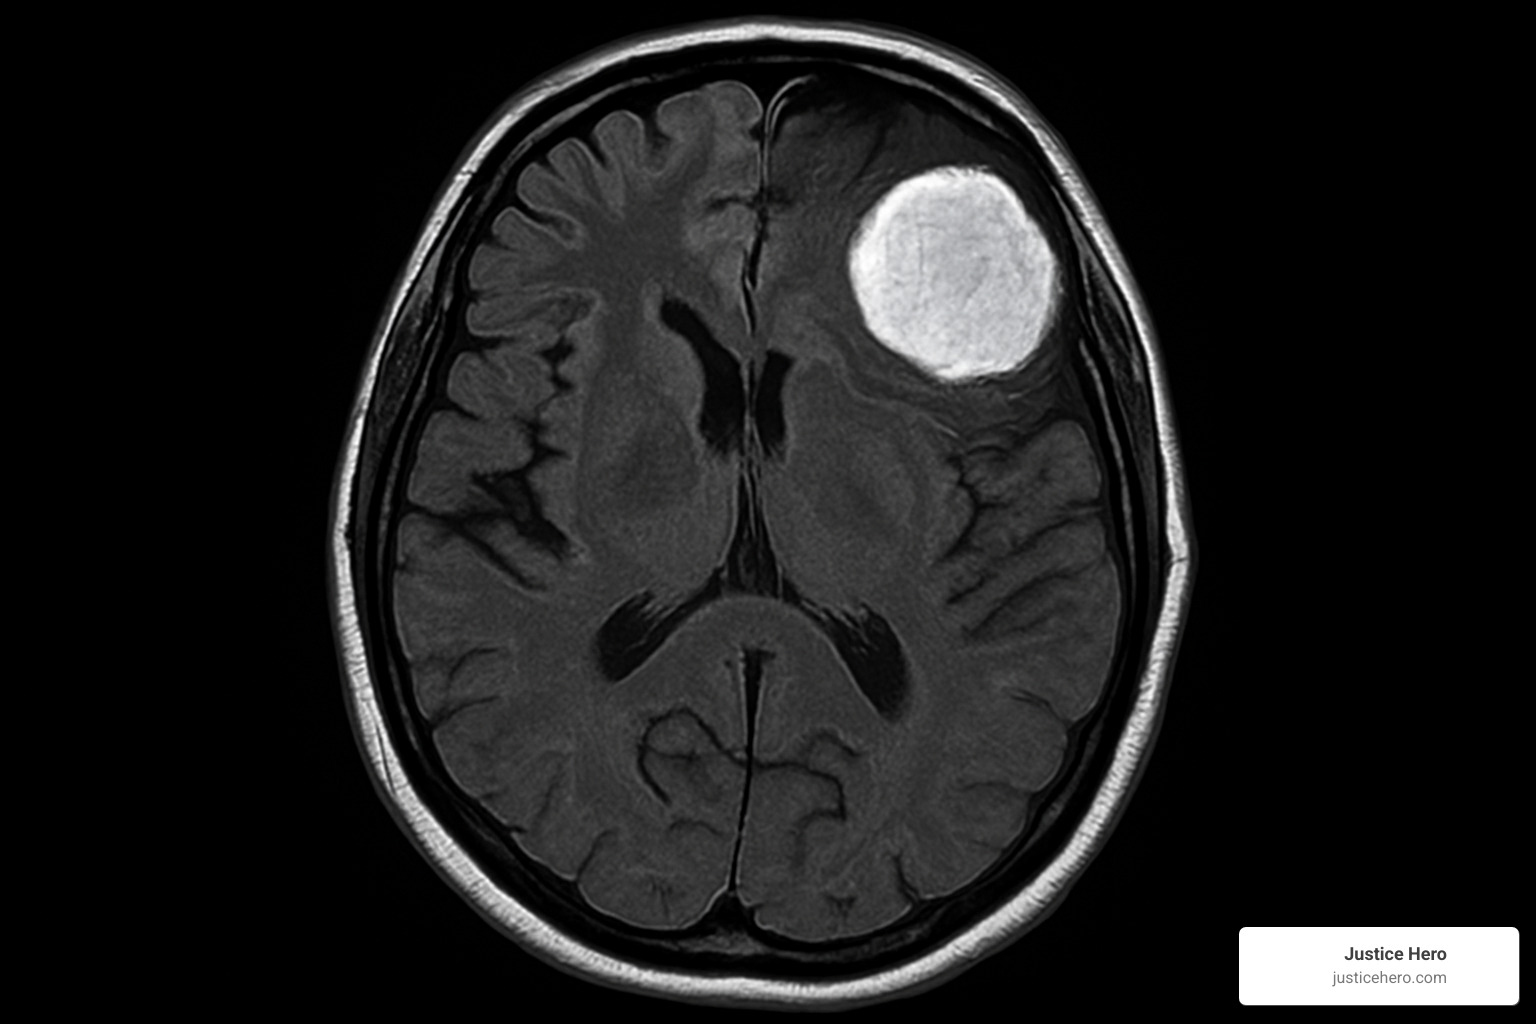

Seek care if headaches intensify, vision blurs, or any combination of the symptoms above appears. Doctors start with a neurological exam and usually order an MRI with contrast, the gold standard for spotting meningiomas.

Bring a symptom diary, your Depo-Provera injection dates, and family medical history to the appointment. If imaging confirms a tumor, your team will discuss monitoring versus surgery depending on size, location, and symptom severity.